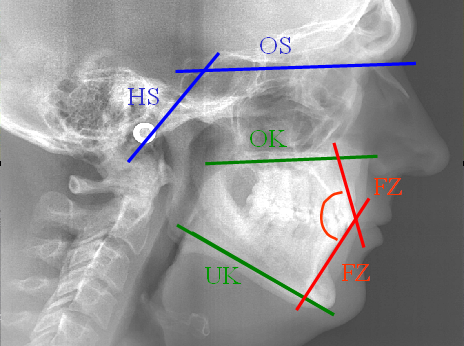

จากภาพถ่ายรังสีเอกซ์ทางด้านข้างศีรษะทำให้ทราบถึงลักษณะโครงสร้างของกระดูกกะโหลกศีรษะส่วนที่ค้ำจุนบริเวณใบหน้า ทิศทางการเจริญพัฒนาของกระดูกขากรรไกรและแนวของแกนฟัน จากผลการวิเคราะห์โครงสร้างทางร่างกายต่างๆ ทำให้ทันตแพทย์จัดฟันได้รับข้อมูลที่สำคัญต่างๆในการวางแผนการรักษา เช่น

-ค่าการวัดความสัมพันธ์ตำแหน่งและขนาดของกระดูกขากรรไกรต่อกะโหลกศีรษะ

-ตำแหน่งและความสัมพันธ์ระหว่างกระดูกช่วงล่างของกะโหลกศีรษะส่วนที่ป้องกันสมอง

-ค่าการวัดแนวของแกนฟันหน้าและฟันกราม

-ลักษณะและผลการวิเคราะห์โครงสร้างกระดูกกะโหลกศีรษะส่วนที่ค้ำจุนบริเวณใบหน้า

-ค่าการวัดทิศทางและระดับการเจริญพัฒนาของกระดูกส่วนต่างๆของกะโหลกศีรษะส่วนที่ค้ำจุนบริเวณใบหน้า

-ภาพแสดงเส้นทางเดินหายใจ (คับแคบผิดปกติหรือไม่)